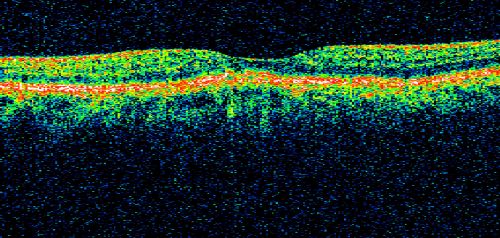

Basal Laminar (cuticular) Drusen both eyes 60 Year Old Woman

60-year-old woman with minimal vision loss. Vision OD is 20/30 OS 20/40